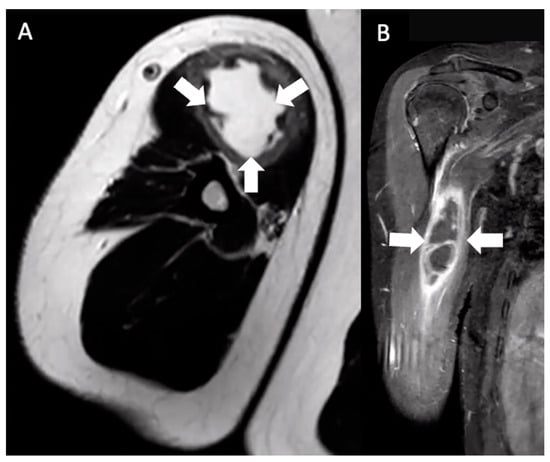

Six months after the booster, the patient discovered a mass in the anteromedial right upper arm. He reported 3-out-of-10 pain in his right arm, but his main concerns were limited range of motion (ROM) attributed to a feeling of “heaviness” and his concern of a possible malignancy. The lump was described as a solid, “golf-ball-sized” mass without induration, warmth, discoloration, or urticaria. Four days after noticing the mass, he consulted his primary care physician, who ordered a magnetic resonance imaging (MRI) of his right arm that showed a 7.4 × 3.7 × 2.6 cm mass in the short head of the right biceps with mild hemorrhagic fluid abutting the humerus but with no evidence of cortical erosion or bone marrow signal change (Figure 1).

Figure 1. Multiplanar MRI of the right upper arm taken five days after identifying the mass and six months after receiving the booster dose. Axial T2 (A) and coronal T1W FS (B) images show an ill-defined fluid signal within the short head, right biceps muscle belly. The area involved extended from the muscle belly to the proximal humeral cortex, measuring approximately 7.4 × 3.7 × 2.6 cm (arrows).